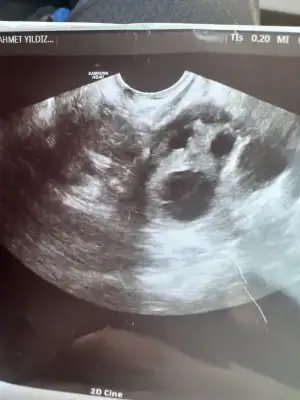

Kızlar rahim ultrason anlayan var mı yumurtan çatlamış dedi doktor ama kanda gebelik çıkmadı lütfen bilen varsa yorum yapabilir mi kızlar 🥹🥹🥹

canım 18.5 mm ölçmüş yumurta bu çatladığını nasıl anladı acaba 🫣 benim dr umda yltrasonda gördü bu ay banada muhtemelen çatlamış içi kanlanmış yumurtanın dedi

Canım bana da çatlamış görünüyor dedi kafam çok karıştı şuan ilişki olmalı mı yoksa şansım yok mu bu ay regl olur muyum sence